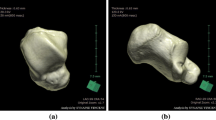

3D images of bilateral lower limb long bones, including the femur, tibia, fibula, and first metatarsus, were virtually reconstructed on the automated CT image analyzing system Volume Analyzer SYNAPSE VINCENT version 3 (FUJIFILM Medical Co., Ltd., Tokyo), identifying each bone shape based on the manufacturer’s graph-cut algorithm, which automatically estimates the CT value distribution and optimal boundary for region segmentation of the bones without users’ intervention [23, 34, 35]. The first metatarsus was chosen because it is a well-preserved foot bone in decomposed bodies and easy to identify when recovered separately [36]. Measured parameters were bone mass volume (cm3), maximum (max.) length (mm) (vertical distance between proximal and distal endpoints) (Supplementary Fig. S1), and the mean CT attenuation (HU) value and total CT attenuation (HU) value (mean HU × bone volume). The mean CT attenuation (HU) value was automatically provided for the whole extracted bone. Manual 3D measurement of the bone length was performed by three independent observers, and intraobserver and interobserver precisions were examined by applying three widely used precision estimates: the technical error of measurement (TEM), the relative technical error of measurement (rTEM), and the coefficient of reliability (R) [16]. Virtual measurements of the maximum bone length were compared with the manual measurements using skeletonized dry bone samples of the femur, tibia, and fibula (n = 7 for each) to examine the reliability. These measurements were repeated two times for each bone.

3D images of individual bones were virtually reconstructed on the automated CT image analyzing system two times in all cases. The reproducibilities of the extracted bone volume and CT density were 100.0 %. In manual measurements of bone lengths, intraobserver precisions were TEM = 0.149–1.316, rTEM < 1.5 %, and R > 0.95; interobserver precisions were TEM = 0.752–1.878, rTEM < 2.0 %, and R > 0.95 (Table 1). The differences between the virtual measurements using the volume analyzer and manual measurements of skeletonized dry bone samples of the femur, tibia, and fibula were 0–2 mm (errors within 0.005 % for each bone length).

Hishmat AM, Michiue T, Sogawa N, Oritani S, Ishikawa T, Hashem MA, Maeda H (2014) Efficacy of automated three-dimensional image reconstruction of the femur from postmortem computed tomography data in morphometry for victim identification. Leg Med (Tokyo) 16:114–117